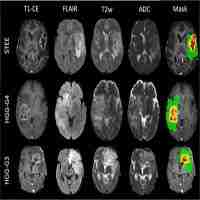

| Abstract | Background IDH1-wildtype glioblastoma multiforme (IDHwt-GBM) is a highly heterogeneous and aggressive brain tumour characterised by a dismal prognosis and significant challenges in accurately predicting patient outcomes. To address these issues and personalise treatment approaches, we aimed to develop and validate robust multiomics molecular subtypes of IDHwt-GBM. Through this, we sought to uncover the distinct molecular signatures underlying these subtypes, paving the way for improved diagnosis and targeted therapy for this challenging disease. Methods To identify stable molecular subtypes among 184 IDHwt-GBM patients from TCGA, we used the consensus clustering method to consolidate the results from ten advanced multiomics clustering approaches based on mRNA, lncRNA, and mutation data. We developed subtype prediction models using the PAM and machine learning algorithms based on mRNA and MRI data for enhanced clinical utility. These models were validated in five independent datasets, and an online interactive system was created. We conducted a comprehensive assessment of the clinical impact, drug treatment response, and molecular associations of the IDHwt-GBM subtypes. Results In the TCGA cohort, two molecular subtypes, class 1 and class 2, were identified through multiomics clustering of IDHwt-GBM patients. There was a significant difference in survival between Class 1 and Class 2 patients, with a hazard ratio (HR) of 1.68 [1.15–2.47]. This difference was validated in other datasets (CGGA: HR = 1.75[1.04, 2.94]; CPTAC: HR = 1.79[1.09–2.91]; GALSS: HR = 1.66[1.09–2.54]; UCSF: HR = 1.33[1.00–1.77]; UPENN HR = 1.29[1.04–1.58]). Additionally, class 2 was more sensitive to treatment with radiotherapy combined with temozolomide, and this sensitivity was validated in the GLASS cohort. Correspondingly, class 2 and class 1 exhibited significant differences in mutation patterns, enriched pathways, programmed cell death (PCD), and the tumour immune microenvironment. Class 2 had more mutation signatures associated with defective DNA mismatch repair (P = 0.0021). Enriched pathways of differentially expressed genes in class 1 and class 2 (P-adjust < 0.05) were mainly related to ferroptosis, the PD-1 checkpoint pathway, the JAK-STAT signalling pathway, and other programmed cell death and immune-related pathways. The different cell death modes and immune microenvironments were validated across multiple datasets. Finally, our developed survival prediction model, which integrates molecular subtypes, age, and sex, demonstrated clinical benefits based on the decision curve in the test set. We deployed the molecular subtyping prediction model and survival prediction model online, allowing interactive use and facilitating user convenience. Conclusions Molecular subtypes were identified and verified through multiomics clustering in IDHwt-GBM patients. These subtypes are linked to specific mutation patterns, the immune microenvironment, prognoses, and treatment responses. |